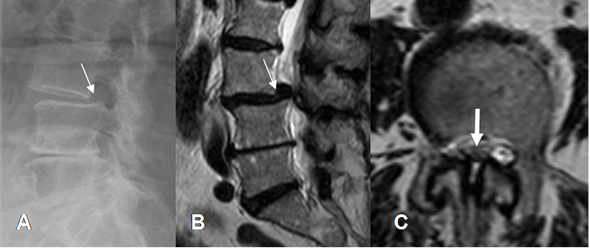

La afectación de la columna cervical y lumbar, produce osteofitos, disminución en la amplitud de los espacios e hipertrofia de articulaciones intervertebrales, con canal estrecho asociado. (Fig 12, 13, 14 y 15).

Fig 13. Artropatía degenerativa.

A y B: TAC cervical axial. Osteofitos anteriores e hipertrofia de articulación intervertebral derecha, que disminuye la amplitud del agujero de conjunción. (Flecha negra).